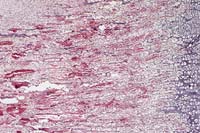

Case 19-1. Rib. The thin cartilage trabeculae arising from the epiphysis (right) show no ossification. Where partially mineralized, they have a scalloped edge, suggesting osteoclastic resorption. Note the increased cortical fibrous tissue (upper left). 4X

AFIP Diagnosis: Bone, vertebra: Osteoporosis, with compression fracture and fibrous osteodystrophy, Suffolk, ovine.

Nutritional imbalances which can result in osteoporosis include starvation; deficiencies of calcium, phosphorus, or copper; and excess of molybdenum. Calcium deficiency uncomplicated by vitamin D and/or phosphorus deficiency rarely, if ever, occurs as a natural disease. In contrast, complicated calcium deficiency is common.2 In both young and adult animals, this results in a loss of cancellous bone. Bones with a high trabecular component, such as verebrae, are most severely affected. In mature animals, calcium deficiency may be asymptomatic, but in young animals pathologic trabecular bone fractures may occur. Often the parathyroid glands are enlarged due to secondary hyperplasia. This leads to increased osteoclastic resorption. Fibrous osteodystrophy may result, as in this case, but is usually less extensive than that seen in the osteodystrophy of calcium deficiency secondary to phosphorus excess.2 The vertebra from this lamb exhibits marked endocortical and mild marrow cavity fibrosis, both resulting from fibrous osteodystrophy. Although few osteoclasts are demonstrable, multiple scalloped edges on bone trabeculae are convincing evidence of increased resorption.